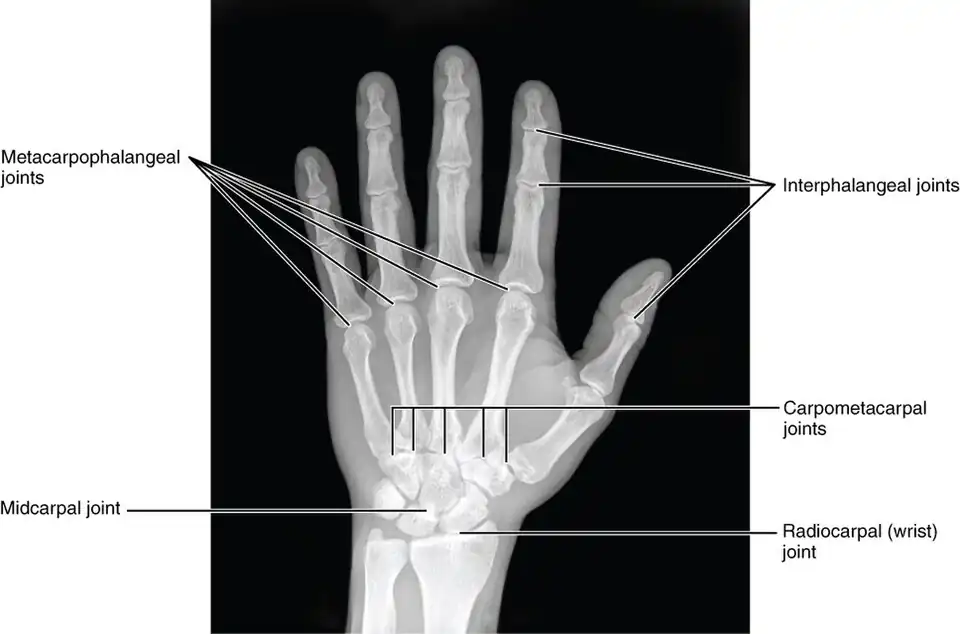

Articulations

Besides the metacarpophalangeal joints, the metacarpal bones articulate by carpometacarpal joints as follows:

- the first with the trapezium;

- the second with the trapezium, trapezoid, capitate and third metacarpal;

- the third with the capitate and second and fourth metacarpals;

- the fourth with the capitate, hamate, and third and fifth metacarpals;

- and the fifth with the hamate and fourth metacarpal;

Carpometacarpal joints of the left hand. Thumb on left. -